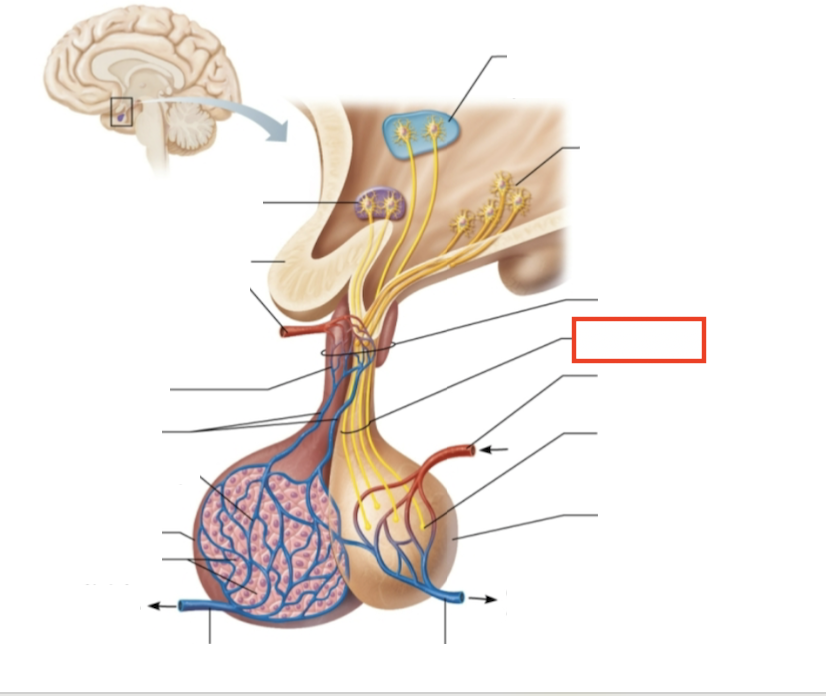

What structure is highlighted?

hypothalamic neurons in the paraventricular nuclei

What structure is highlighted?

neurons in the ventral hypothalamus

What structure is highlighted?

infundibulum (connecting stalk)

What structure is highlighted?

hypothalamic-hypophyseal tract

What structure is highlighted?

inferior hypophyseal artery

What structure is highlighted?

neurohypophysis (storage area for hypothalamic hormones)

What structure is highlighted?

posterior pituitary

What molecules are produced here?

oxytocin, ADH

What structure is highlighted?

venule

What structure is highlighted?

venule

What molecules are produced here?

TSH, FSH, LH, ACTH, GH, PRL

What structure is highlighted?

secretory cells of adenohypophysis

What structure is highlighted?

anterior pituitary

What structure is highlighted?

secondary capillary plexus

What structure is highlighted?

hypophyseal portal veins

What structure is highlighted?

primary capillary plexus

What structure is highlighted?

superior hypophyseal artery

What structure is highlighted?

superior hypophyseal artery

What structure is highlighted?

optic chiasma

What structure is highlighted?

hypothalamic neurons in the supraoptic nuclei